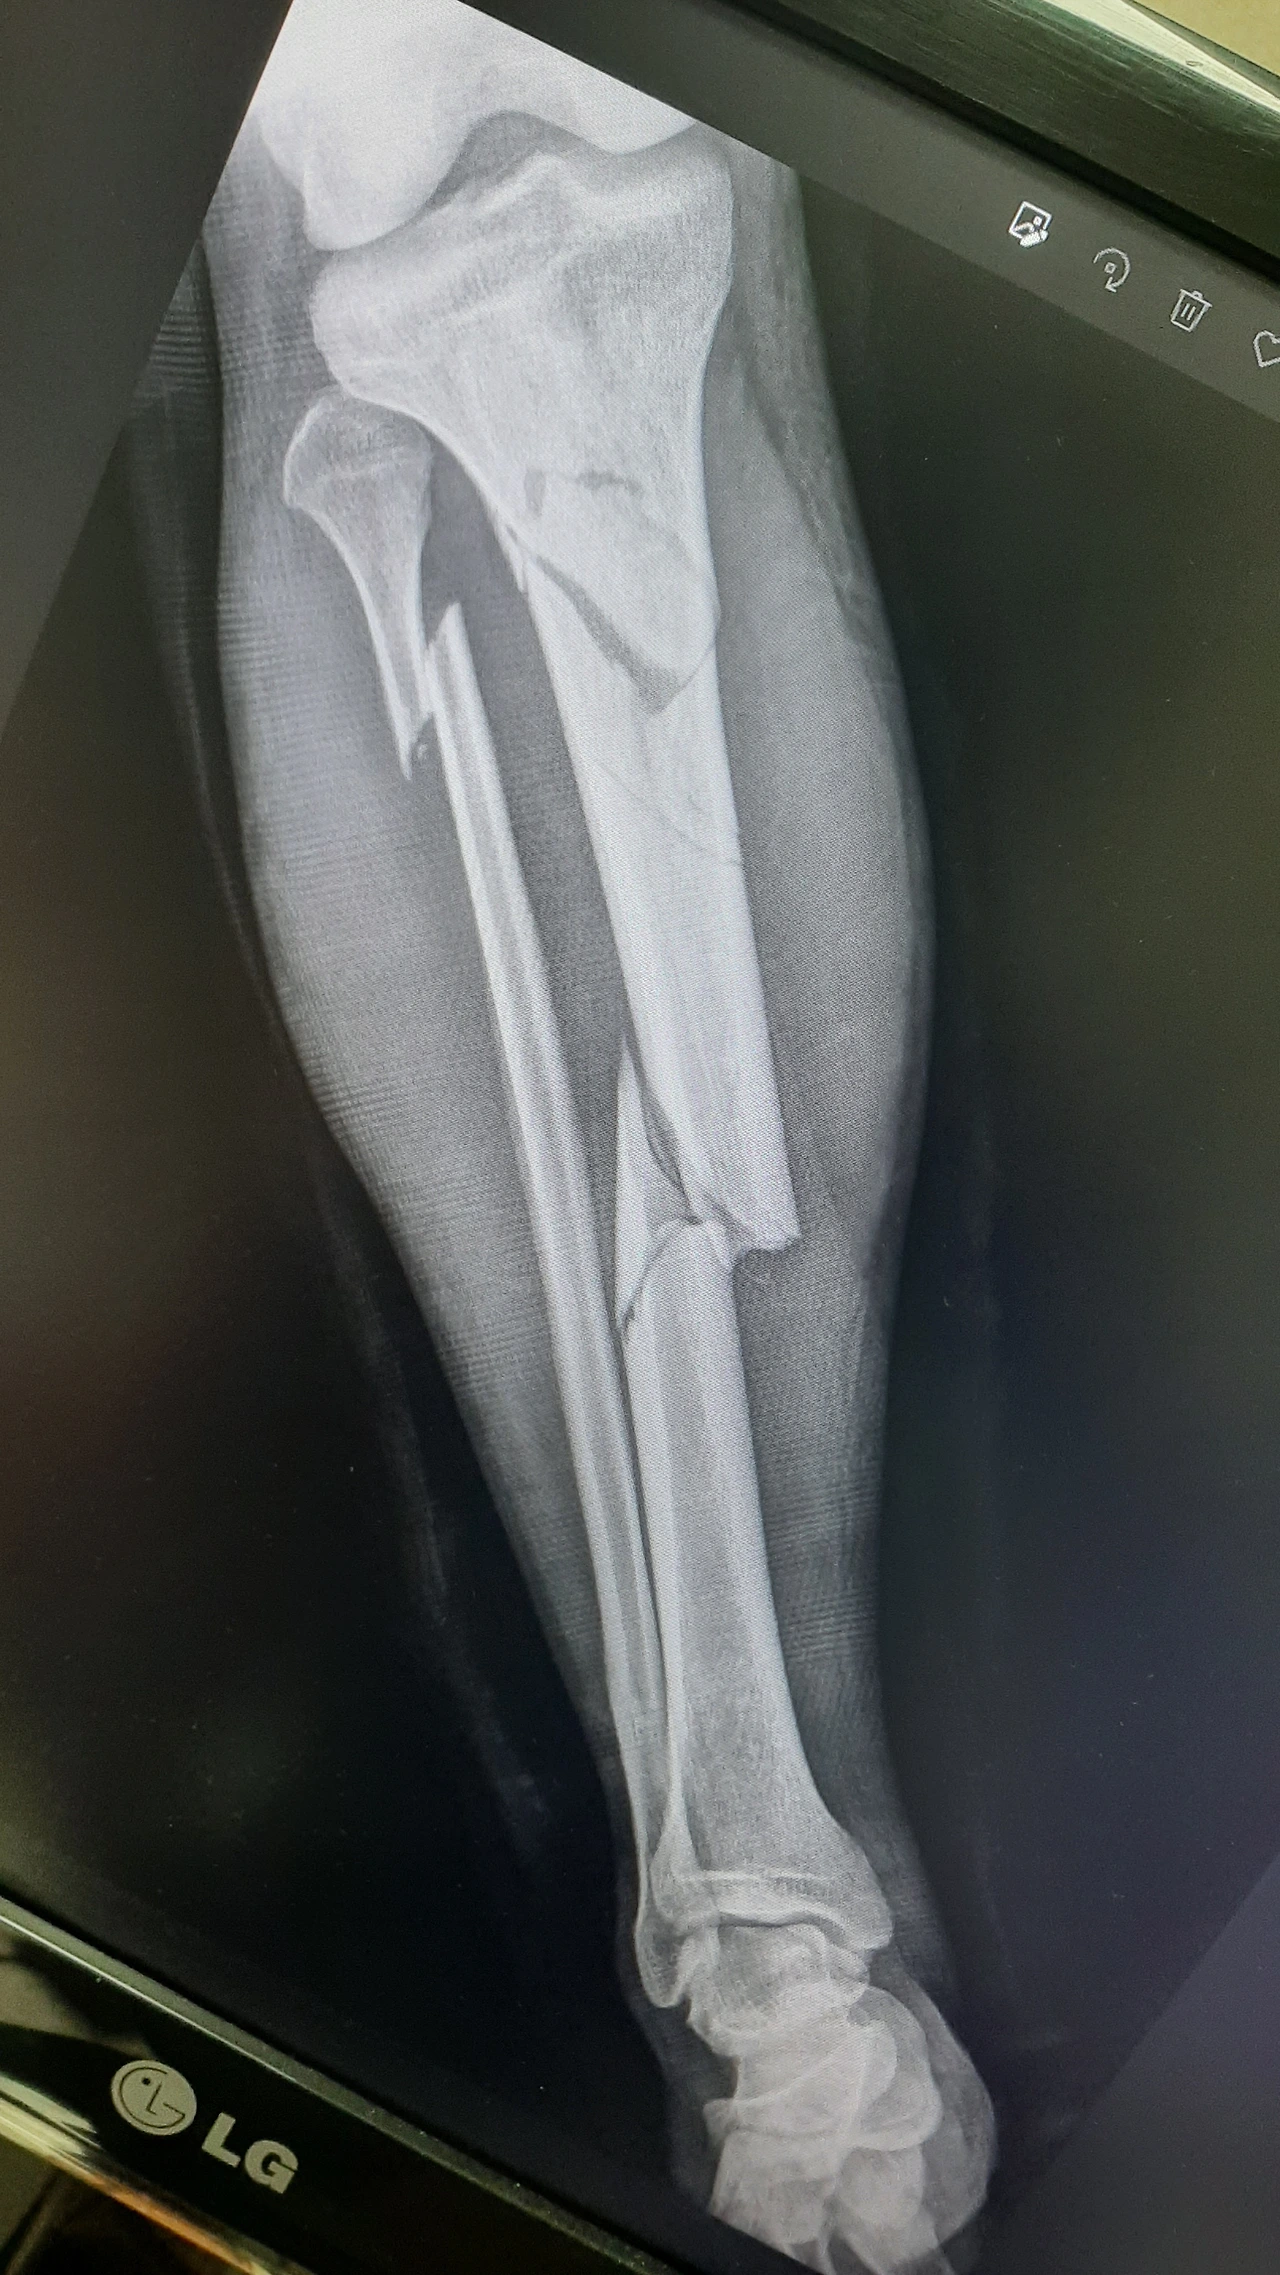

2022년 7월 13일 골절 당시